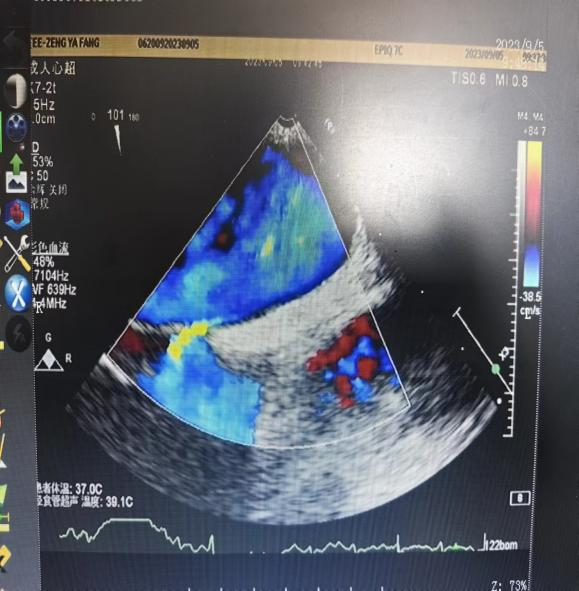

16岁的小曾是一名高二学生,多年来一直饱受头痛的困扰,每次发作都让她难以忍受,曾经多次在其他医院进行头颅CT、MRI检查及治疗,但都找不到具体原因,频繁发作的头痛已经严重影响了她的学习和休息。日前,小曾来到我院心血管内科门诊就诊,通过完善发泡试验及经食道心脏彩超,找出了小曾头痛的“元凶”——心脏卵圆孔未闭。

我院心血管内科团队结合患者情况综合分析病情,组织开展多次讨论,并与患者及家属进行充分沟通,最终决定为小曾行卵圆孔未闭封堵术。术前,心血管内科医疗团队为患者完善必要辅助检查、排除手术禁忌。术中,陈小设主任带领团队与介入室的医护人员默契配合,通过微创介入手术,成功将卵圆孔未闭封堵器植入未闭的卵圆孔处,封堵住心脏“小洞”,顺利完成手术!术后复查彩超显示卵圆孔封堵完好,未见残余分流。患者术后恢复良好,顺利出院。出院后,患者头痛症状缓解,摆脱了困扰她多年的头痛烦恼。